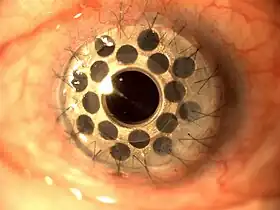

Penetrating keratoplasty

A trephine (a circular cutting device), which removes a circular disc of cornea, is used by the surgeon to cut the donor cornea. A second trephine is then used to remove a similar-sized portion of the patient's cornea. The donor tissue is then sewn in place with sutures.

Antibiotic eyedrops are placed, the eye is patched, and the patient is taken to a recovery area while the effects of the anesthesia wear off. The patient typically goes home following this and sees the doctor the following day for the first postoperative appointment.